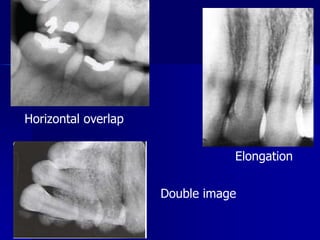

Technique & Projection errorsb. Film placmentartifactDouble imageWhen an exposed film is re-exposed the resulting film will have 2 superimposed images

Technique & Projection errorsc. Projection errorsIncorrect vertical angulationIt will lead to:Elongated image due to insufficient v. angulation ( too flat), or

Shortened image due to excessive v. angulation ( too steep)Technique & Projection errorsc. Projection errors

Technique & Projection errorsc. Projection errorsIncorrect horizontal angulationIs the appearance of the interproximal surfaces of the adjacent teeth over each other. This is due to improper H.A. due to improper alignment of the C.R. through the contact points i.e. not // to interproximal surfaces.